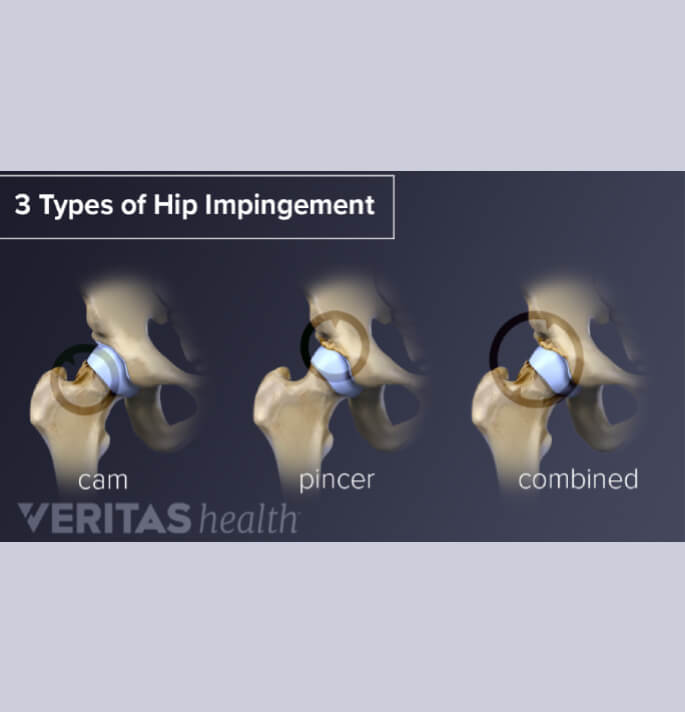

Femorale acetabulaire impingement

Aan de femorale zijde weerhouden we hoofdzakelijk het CAM letsel en aan de acetabulaire zijde het PINCER letsel of een combinatie van beide welke kunnen leiden tot femoro acetabulaire impingement, met labrum pathologie en versnelde arthrose tot gevolg

Mits voldoende tijdig ontdekt kan artroscopische resectie van deze letsels het versneld optreden van artrose voorkomen of toch vertragen.